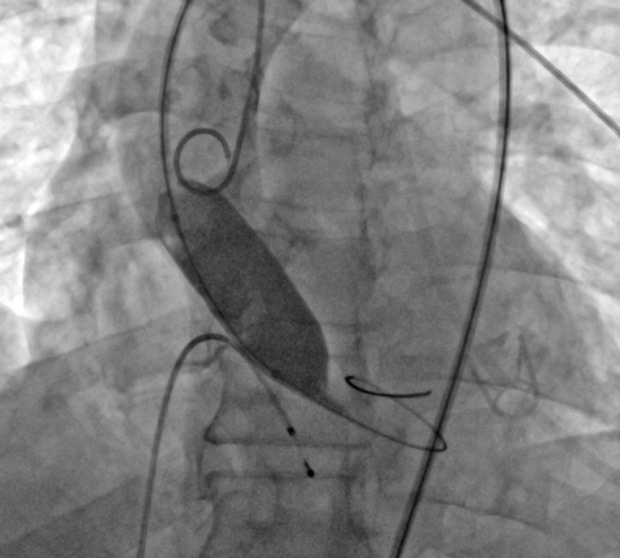

张景昌教授领导的团队对病例进行了多学科的综合分析评估。他们计划通过右侧股动脉入路,首选使用L32号VenusA-Valve瓣膜进行手术。此外,他们还使用了VenusA-Pro第三代可回收输送系统,相较于第二代输送系统,该系统具有更好的推送性和柔顺性。同时,他们对海波管进行了改进,在不降低推送性的同时提高了系统的柔顺性。这些改进旨在确保瓣膜的稳定释放、改善同轴性并降低冠脉风险。在瓣膜释放后,团队会结合造影和超声情况进行观察。

在手术过程中,DSA显示器起到了重要作用。

在瓣膜释放完成后,立刻进行了造影和超声评估。结果显示,患者跨瓣压差显著降低,超声检查没有发现瓣周漏,全主动脉和入路也没有出现并发症。手术圆满成功。

术中片段: